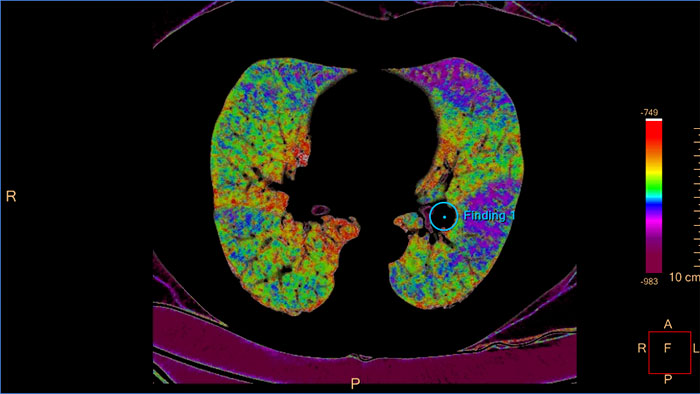

CT COPD helps visualize and quantify the destructive process of diffuse lung disease (e.g. emphysema). The application provides a guided workflow for airway analysis, reviewing and measuring airway lumen, and assessing air trapped.